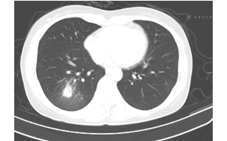

21例患者均行肺电子计算机断层扫描(CT)检查,提示双肺单发(2例)或多发(19例)的斑片状、条片状、团片状、结节状、磨玻璃样高密度影,边界模糊,其中2例病灶中出现含气支气管影。单个病灶直径1~5 cm,可为单肺(9例,其中5例为右肺,4例为左肺)或双肺(12例)受累,在肺叶、段分布上无明显特异性(图1、图2、图3)。

本组病例中,患者年龄主要集中在20~40岁,既往健康情况良好,大部分患者表示既往有麻疹疫苗接种史,但均不能提供末次麻疹疫苗接种时间。患者病程自限,热程均在一周以内,平均热程为(4.5±1.7)d,1例患者仅发热半天。患者发热多在出疹后3 d内迅速退热,状态良好,除肺炎外,其他并发症相对较少且轻,仅1例患者有一过性轻微腹泻,5例患者肝功能轻度异常。患者白细胞计数正常或偏低,提示为病毒性感染。肺炎为本研究中所有患者的主要临床表现,影像学上突出表现为单发或多发的团、片状高密度影,在肺叶、段的分布上无特异性,病灶直径1~5 cm。国内对聚集性流行的不典型麻疹研究发现,成人的肺炎检出率为19.5%~54.9%(经X线检查诊断)[5,6,7],如进行肺部CT检查,则肺炎的检出率则升至31.2%~94.1%[5,7];散发的成人麻疹(包括典型麻疹病例)中肺炎检出率为6.1%~24.1%(经X线检查诊断)[8,9]。国外报道成人麻疹中,肺炎发生率为34%[10]。然而,上述研究显示,不典型成人麻疹患者尽管并发肺炎的概率较高,单个病灶范围可以较大,但咳嗽、胸痛、呼吸困难等症状不重,且病变吸收较快,患者通常一般状态佳,病程自限、预后良好[5,10],本研究结果与之相似。